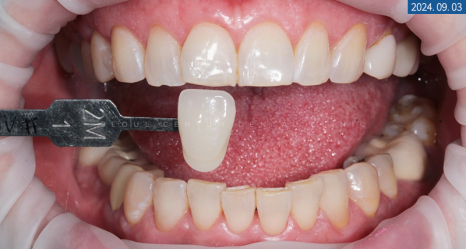

가장 먼저 원하시는 디자인과 색상을 확인하기 위해

쉐이드 체크와 가이드 형태를 보여드렸습니다.

보시고 나서 단정하고 깔끔한 걸로 요청 주셨기에

톤을 1.5단계를 높인 것으로 결정하게 됐습니다.